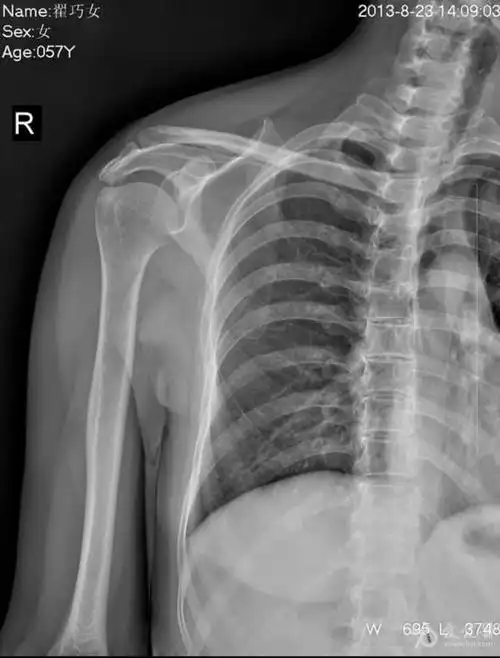

术后右肩关节正位片